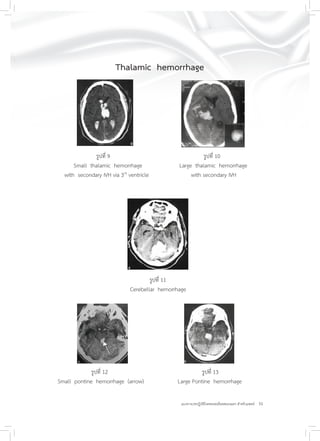

Thalamic hemorrhage

รูปที่ 9 รูปที่ 10

Small thalamic hemorrhage Large thalamic hemorrhage

with secondary IVH via 3rd

ventricle with secondary IVH

รูปที่ 11

Cerebellar hemorrhage

รูปที่ 12 รูปที่ 13

Small pontine hemorrhage (arrow) Large Pontine hemorrhage